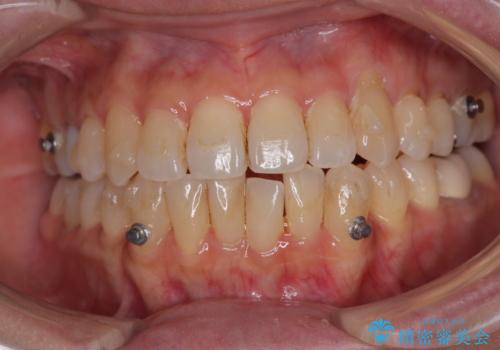

受け口と八重歯を改善 インビザライン矯正治療

- 前歯のデコボコや八重歯を治したいとのことで来院された患者様です。

受け口傾向の骨格であり、前歯はクロスバイトまたは切端咬合となっており、下顎を中心に歯列全体の後方移動を行い、IPR(歯と歯の間を削る)によってデコボコが解消するように設計し、インビザラインにより治療を行うこととしました。

受け口傾向のインビザライン矯正は比較的治療を行いやすいため、きれいに仕上げることができました。舌の突出癖が顕著であったため、改善のためのトレーニングをしっかりと行っていただきました。